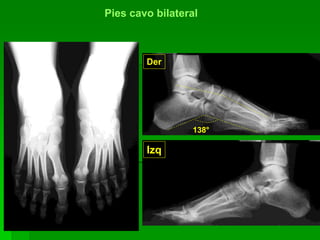

Pié cavo bilateral

Der.

Izq.

Pies cavo bilateral

Der

Izq

138°